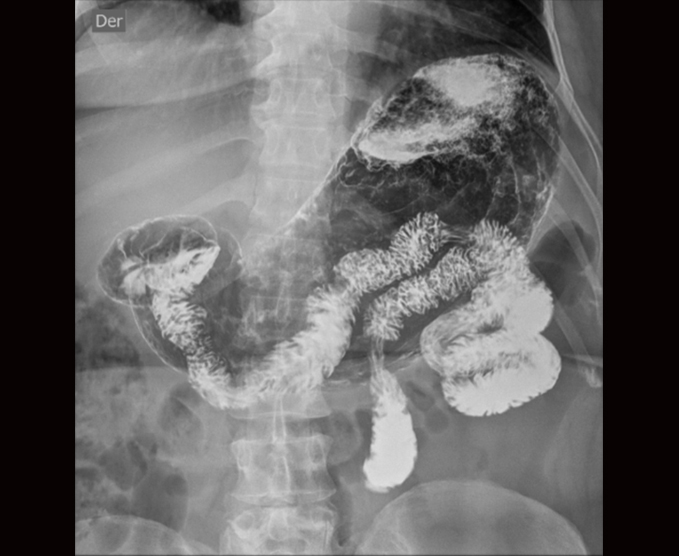

Algunos de nuestros estudios contrastados.

- Colon por enema